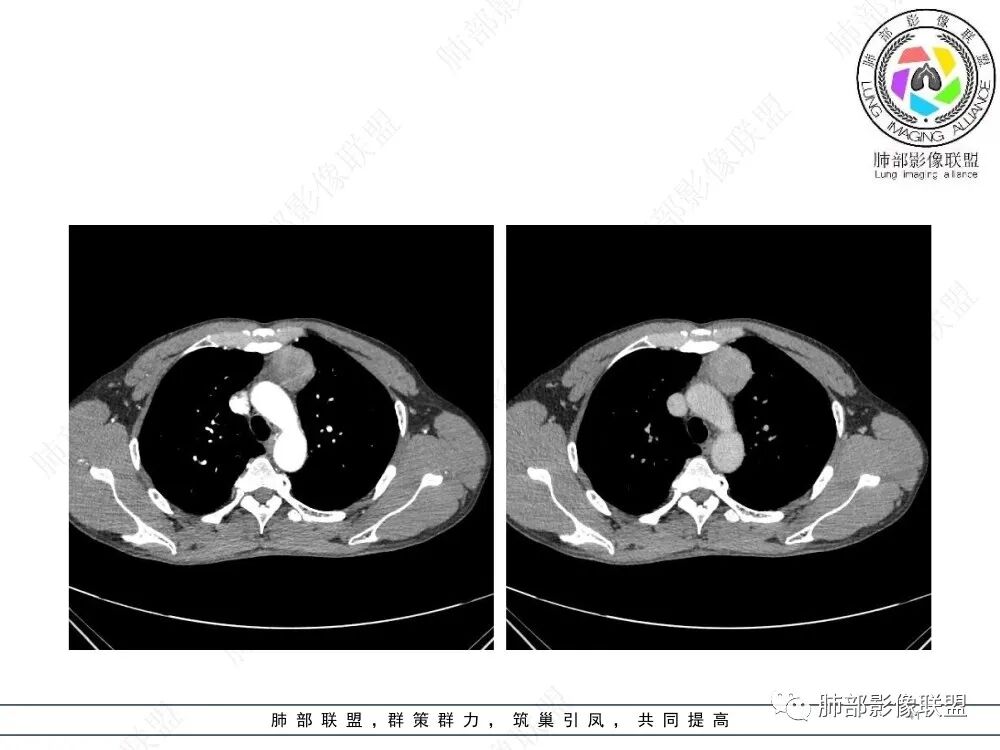

放射小白:男性47岁,前纵隔团块状占位,边界尚清,增强中度强化,内部疑似纤维分隔,常规考虑胸腺瘤可能(A/AB型),鉴别类癌、CD。

Yishion:晨读:纵隔占位,偏侧生长,边界清楚,有浅分叶,强化明显,其内似见纤维分隔,常规考虑胸腺瘤(AB型)。

衡妈🇨🇳:中年男性,前纵隔偏左侧实性占位,密度相对均匀,边缘分叶,周围脂肪结构略模糊,增强后动脉期不均匀强化,有低密度区,纤维分隔显示不清。考虑胸腺瘤B1 B2型。

流心明智:男,47,咳嗽、咳痰1年余。胸部CT:前纵膈偏左类圆形肿块,瘤肺界面清晰光整,纵隔侧部分层面絮状影?平扫密度较均匀,增强后轻度强化,内可见宽带及线样低密度分隔。邻近左上肺受压凹陷。考虑胸腺肿瘤,AB型?胸腺Ca?鉴别淋巴瘤、N源性肿瘤、CD等。

2、影像特点:前纵隔偏左侧软组织影,密度相对均匀,未见明显包膜钙化及实质内钙化,局部边缘浅分叶,周围脂肪间隙密度增高、浑浊,未见侵犯大血管、未见纵隔内淋巴结转移、未见侵犯心包内结构、未见胸膜转移结节、未见肿块沿着纵隔胸膜蔓延,未见胸腔积液。增强后动脉期不均匀强化,未见明显纤维分隔。

3、 病 例 小 结:40岁以上,前纵隔偏侧性生长的肿块,常规考虑胸腺瘤。难点就在于胸腺瘤的分型。但是对于前纵隔占位影像诊断的关键在于区分胸腺囊肿、胸腺瘤、胸腺癌及其他恶性肿瘤。至于胸腺瘤,主要在于判断有无侵袭性。